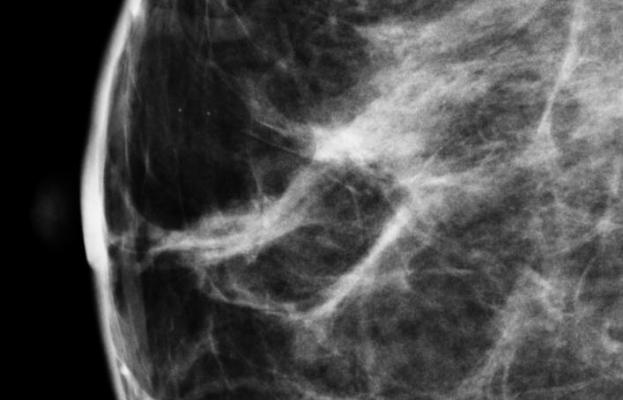

"Too many women are relying on mammography alone to find potential breast cancer,” said Eggl. “For people with dense breast tissue, mammography may be missing early stage breast cancer, giving women a false sense of security that everything is fine. I appreciate the mentoring and leadership of Dr. Nancy Cappello and am grateful knowing my advocacy efforts will benefit women in my home state of North Dakota."